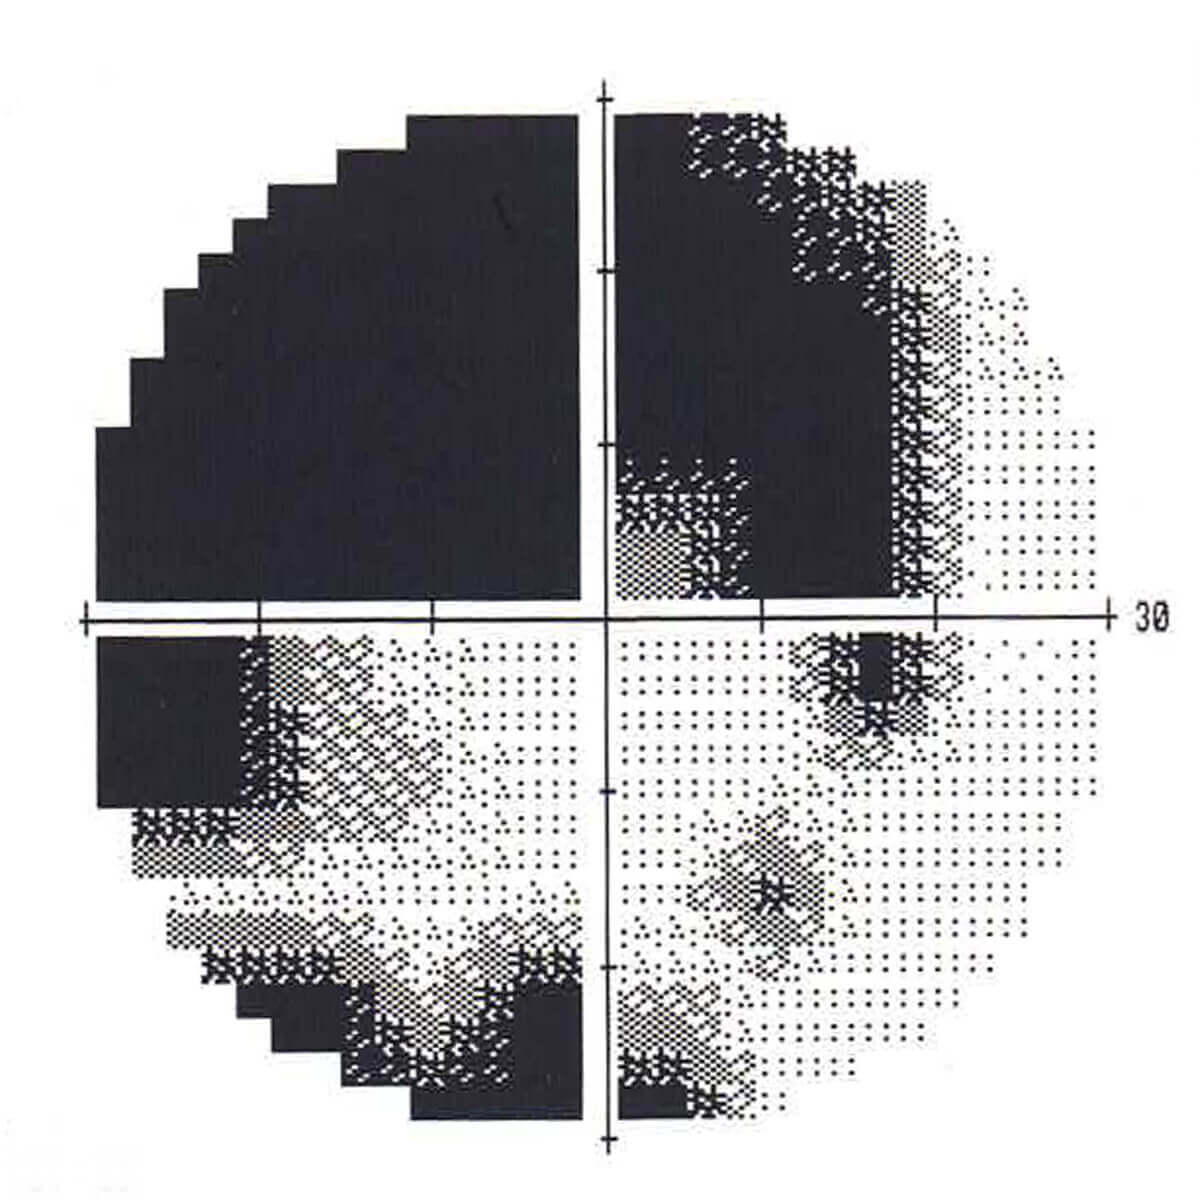

視野検査 緑内障

視神経線維束欠損(NFLD)に一致した視野欠損(黒いところ)を認めます。この欠損の進行の有無を確認することで治療方針を決定していきます。